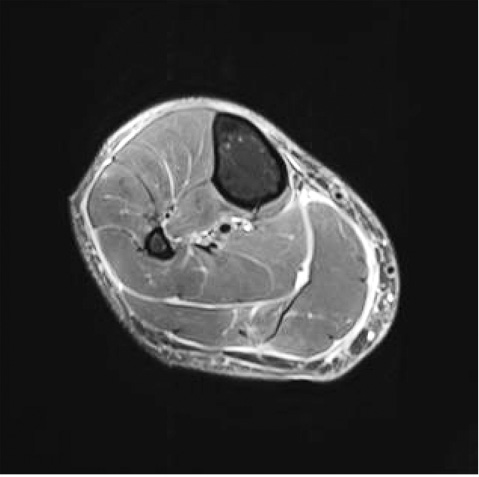

Результати МРТ правої гомілки. На серії МРТ кортикальний шар кісткових елементів правої гомілки нормальної вираженості. Змін магнітно-резонансного (МР)-сигналу від кісткового мозку досліджених кісток гомілки не виявлено, контури кісток чіткі. При наївних сканах на Stir та T2FS послідовностях в усіх м’язах (передньої та більше задньої групи) на досліджуваному рівні відзначається гетерогенно підвищений МР-сигнал внаслідок гідрофільного вмісту між м’язовими волокнами (за типом «пера») (рис. 3, 4).

Рис. 3 та рис. 4. МР-зображення ущільнення, інфільтрації та потовщення підшкірно-жирової клітковини, симптом «пера» та ущільнення фасцій гомілки

Виражено інфільтрована підшкірно-жирова клітковина, потовщена шкіра. Також відзначається підвищений МР-сигнал від усіх фасцій гомілки та деяке їх потовщення (рис. 5, 6).

Рис. 5 та рис. 6. МР-зображення ущільнення, інфільтрації та потовщення підшкірно-жирової клітковини та ущільнення фасцій гомілк

У міжфасціальних просторах мінімальні смужки рідини до 1–2 мм товщиною. У передньо-латеральних відділах середньої третини гомілки визначаються постопераційні зміни (постбіопсійні), інфільтровані прилеглі м’які тканини до місця втручання, наявне незначне скупчення рідини. Судини без патологічних змін. Після введення контрасту всі вище­описані зміни (м’язи, фасції, підшкірно-жирова клітковина) мають підвищене накопичення конт­расту. МР-картина може відповідати проявами патології сполучної тканини — еозинофільному фасциту та потребує гістологічного підтвердження виявлених змін.